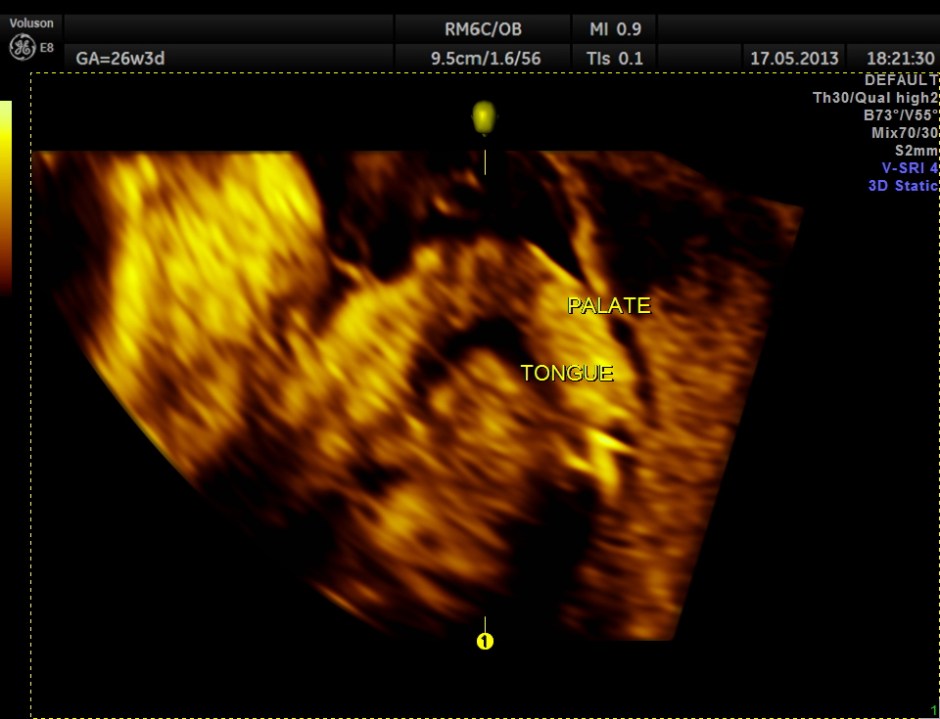

The following images show the face and the palate.

This fetus did not show any oro-facial clefts ; heart and spine appeared normal.